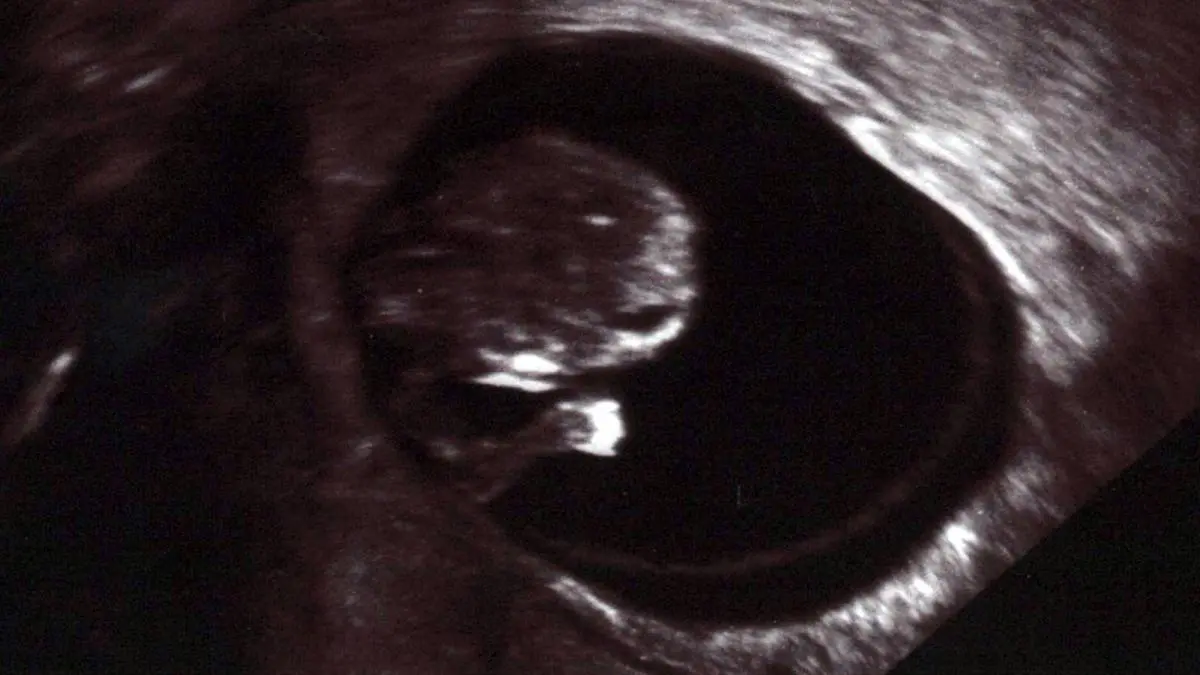

- Ultraschalluntersuchung: Eine Ultraschalluntersuchung kann die Größe und Position des Embryos sowie die Herzaktion zeigen.